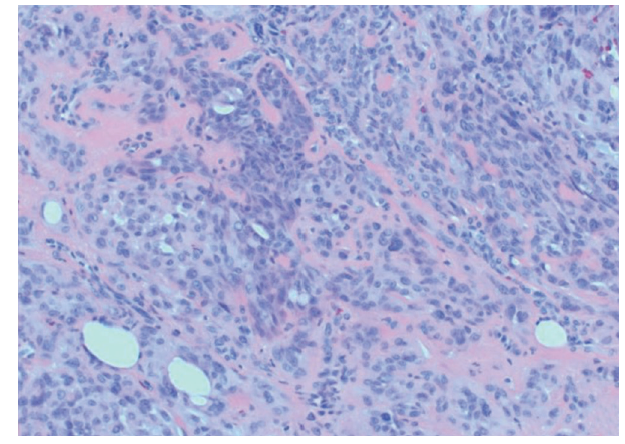

On histology, these tumors appear similar to benign salivary gland mixed tumors.1 The cells have eosinophilic hyaline stroma and plasmacytoid features.5 The stroma may be myxoid, chondroid, fibrous, adipocytic, or osseous.1 Headington8 categorized chondroid syringomas into 2 types, apocrine and eccrine. The eccrine type consists of small, round tubules that are evenly spaced in a myxoid-chondroid matrix, while the apocrine type consists of irregularly branching tubules lined by thicker epitheliaum.1 The HCRCS variant consists of plasmacytoid cells with hyaline cytoplasm in a myxochondroid to hyaline stroma and stains positive for cytokeratin, vimentin, and S100, with inconsistent expression of myoepithelial differentiation markers such as actin and calponin.5 Our patient’s mass had a similar histological appearance and immunohistochemical profile, staining positively for cytokeratin and S100 and focally for calponin. (Figure 1, Figure 2, Figure 3, Figure 4)